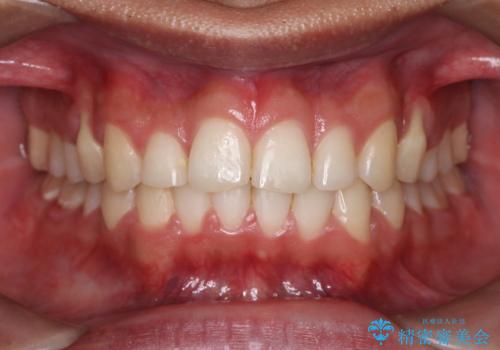

治療途中では咬み合わせの改善を目的としてバイトアップを行い、歯の捻転や叢生を改善しつつ、機能的に安定した咬合を獲得しています。

治療期間は3年2ヵ月と比較的長期となりましたが、見た目の歯並びだけでなく、咬み合わせまでしっかり整えた症例です。

上顎左右4番は90度捻転していたため、改善後歯根露出してしまっているためCTG(歯肉移植)を行う予定です。